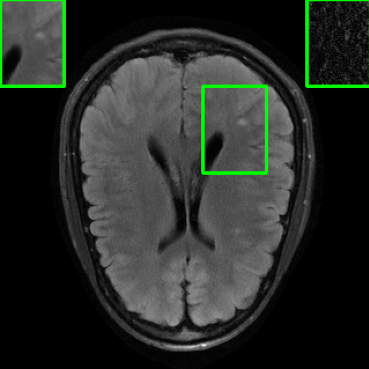

Performance on Data with Lesions: While the previous experiment allowed comparing reconstruction quality with or without planted features, here we test our method on MRI scans with lesions, which are often regions of abnormal or diseased tissue. We utilize the annotated fastMRI+ data666https://github.com/microsoft/fastmri-plus/tree/main to evaluate our method’s image reconstruction capabilities, and compare its outcomes with established baselines. For the training phase, the non-lesion dataset was employed for the global training approach with images whereas LONDN-MRI used adaptively selected images for training (searched from images). In contrast, during the testing phase, we used scans with lesions. The results, as displayed in Table V, indicate that our method achieves substantially higher PSNR values in comparison to the globally trained baseline as well as the LORAKI method. Furthermore, visualizations in Figure 16 clearly demonstrate the superiority of our method, particularly in the nonspecific white matter lesion areas. Thus, both in terms of visual assessment and PSNR values, our approach outperforms the existing baselines and aligns more closely with the ground truth.

| Ground Truth | LORAKI | Global | LONDN-MRI | LONDN-MRI | Oracle |

| (1 iteration) | (2 iterations) | ||||

![]() |

| PSNR = dB | PSNR = 33.21 dB | PSNR = 36.12 dB | PSNR = 36.31 dB | PSNR = 36.54 dB | PSNR = 36.71 |